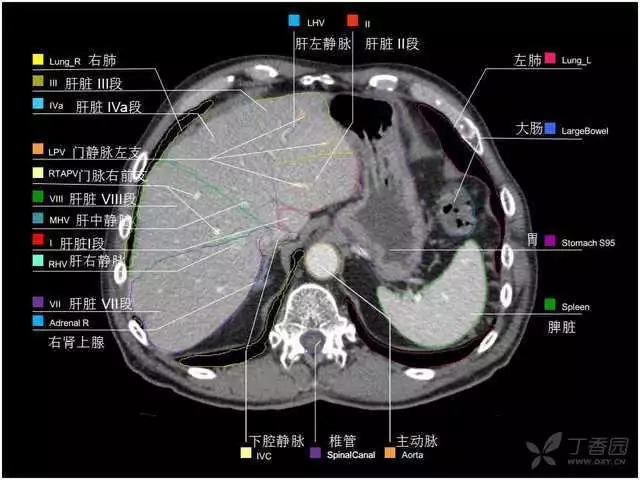

腹部肝脏高清CT断层的图谱

全腹部高清CT图谱,淋巴结彩色图谱,血管解剖图谱大汇总!

肝段,肝内管道的分布规律